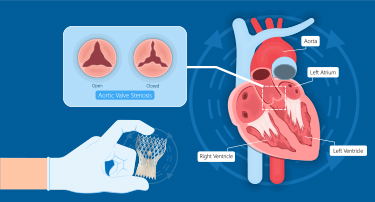

Innovative Heart Valve Solutions That Avoid Open-Heart Surgery

For decades, open-heart surgery was the sole method for repairing or replacing a defective heart valve. Although effective, the old method is marked by giant incisions, extended recovery periods, and jeopardy to elderly or high-risk patients.

TAVI Vs. Open-Heart Surgery: Which Is The Right Choice For You?

For heart valve replacement, patients usually have two primary choices: Transcatheter Aortic Valve Implantation (TAVI) and open-heart surgery. Both involve replacing a faulty aortic valve, but they are very different in approach, recovery period, and applicability to various patient populations. Knowing the main differences, advantages, disadvantages, and success rates can assist you in making an informed choice.

Who Is The Ideal Candidate For TAVI? Understanding Eligibility & Benefits

Transcatheter Aortic Valve Implantation (TAVI) has revolutionized the treatment of severe aortic stenosis, especially for patients who are high-risk candidates for traditional open-heart surgery. This minimally invasive procedure offers a lifeline to many, but determining who stands to benefit the most is crucial.